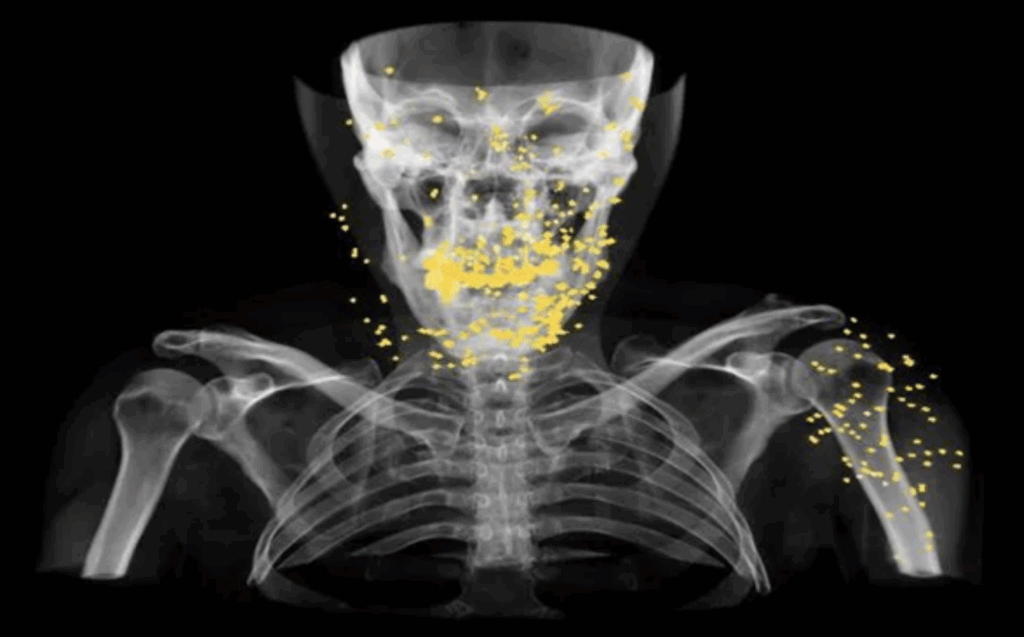

To prepare this report, the medical files of a number of individuals with eye injuries were shared with a global group of ophthalmology specialists. The results of their evaluations show that the pattern of eye injuries points to deliberate targeting. According to these specialists, the trauma caused by blindness is psychologically comparable to the experience of being diagnosed with cancer. This conclusion underscores the profound physical and psychological damages inflicted by this suppression tactic.

Medical records of numerous victims who were shot in the head and eyes with shotgun projectiles demonstrate that the ammunition was discharged at close range. One such case is that of Hossein, a middle-aged man who lost both eyes and was permanently blinded. His medical file documents the presence of at least 300 pellets embedded around his eyes. At the time, he and his wife were attending the 40th-day memorial ceremony for Hadis Najafi, a young protester, in Karaj in Alborz Province. Witness accounts and medical evidence indicate that Hossein was shot with a shotgun while lying motionless on the ground as an act of submission.[94] Out of fear of reprisals by the Iranian government, he has chosen to remain anonymous.